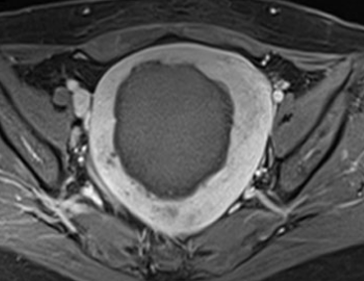

시술 후